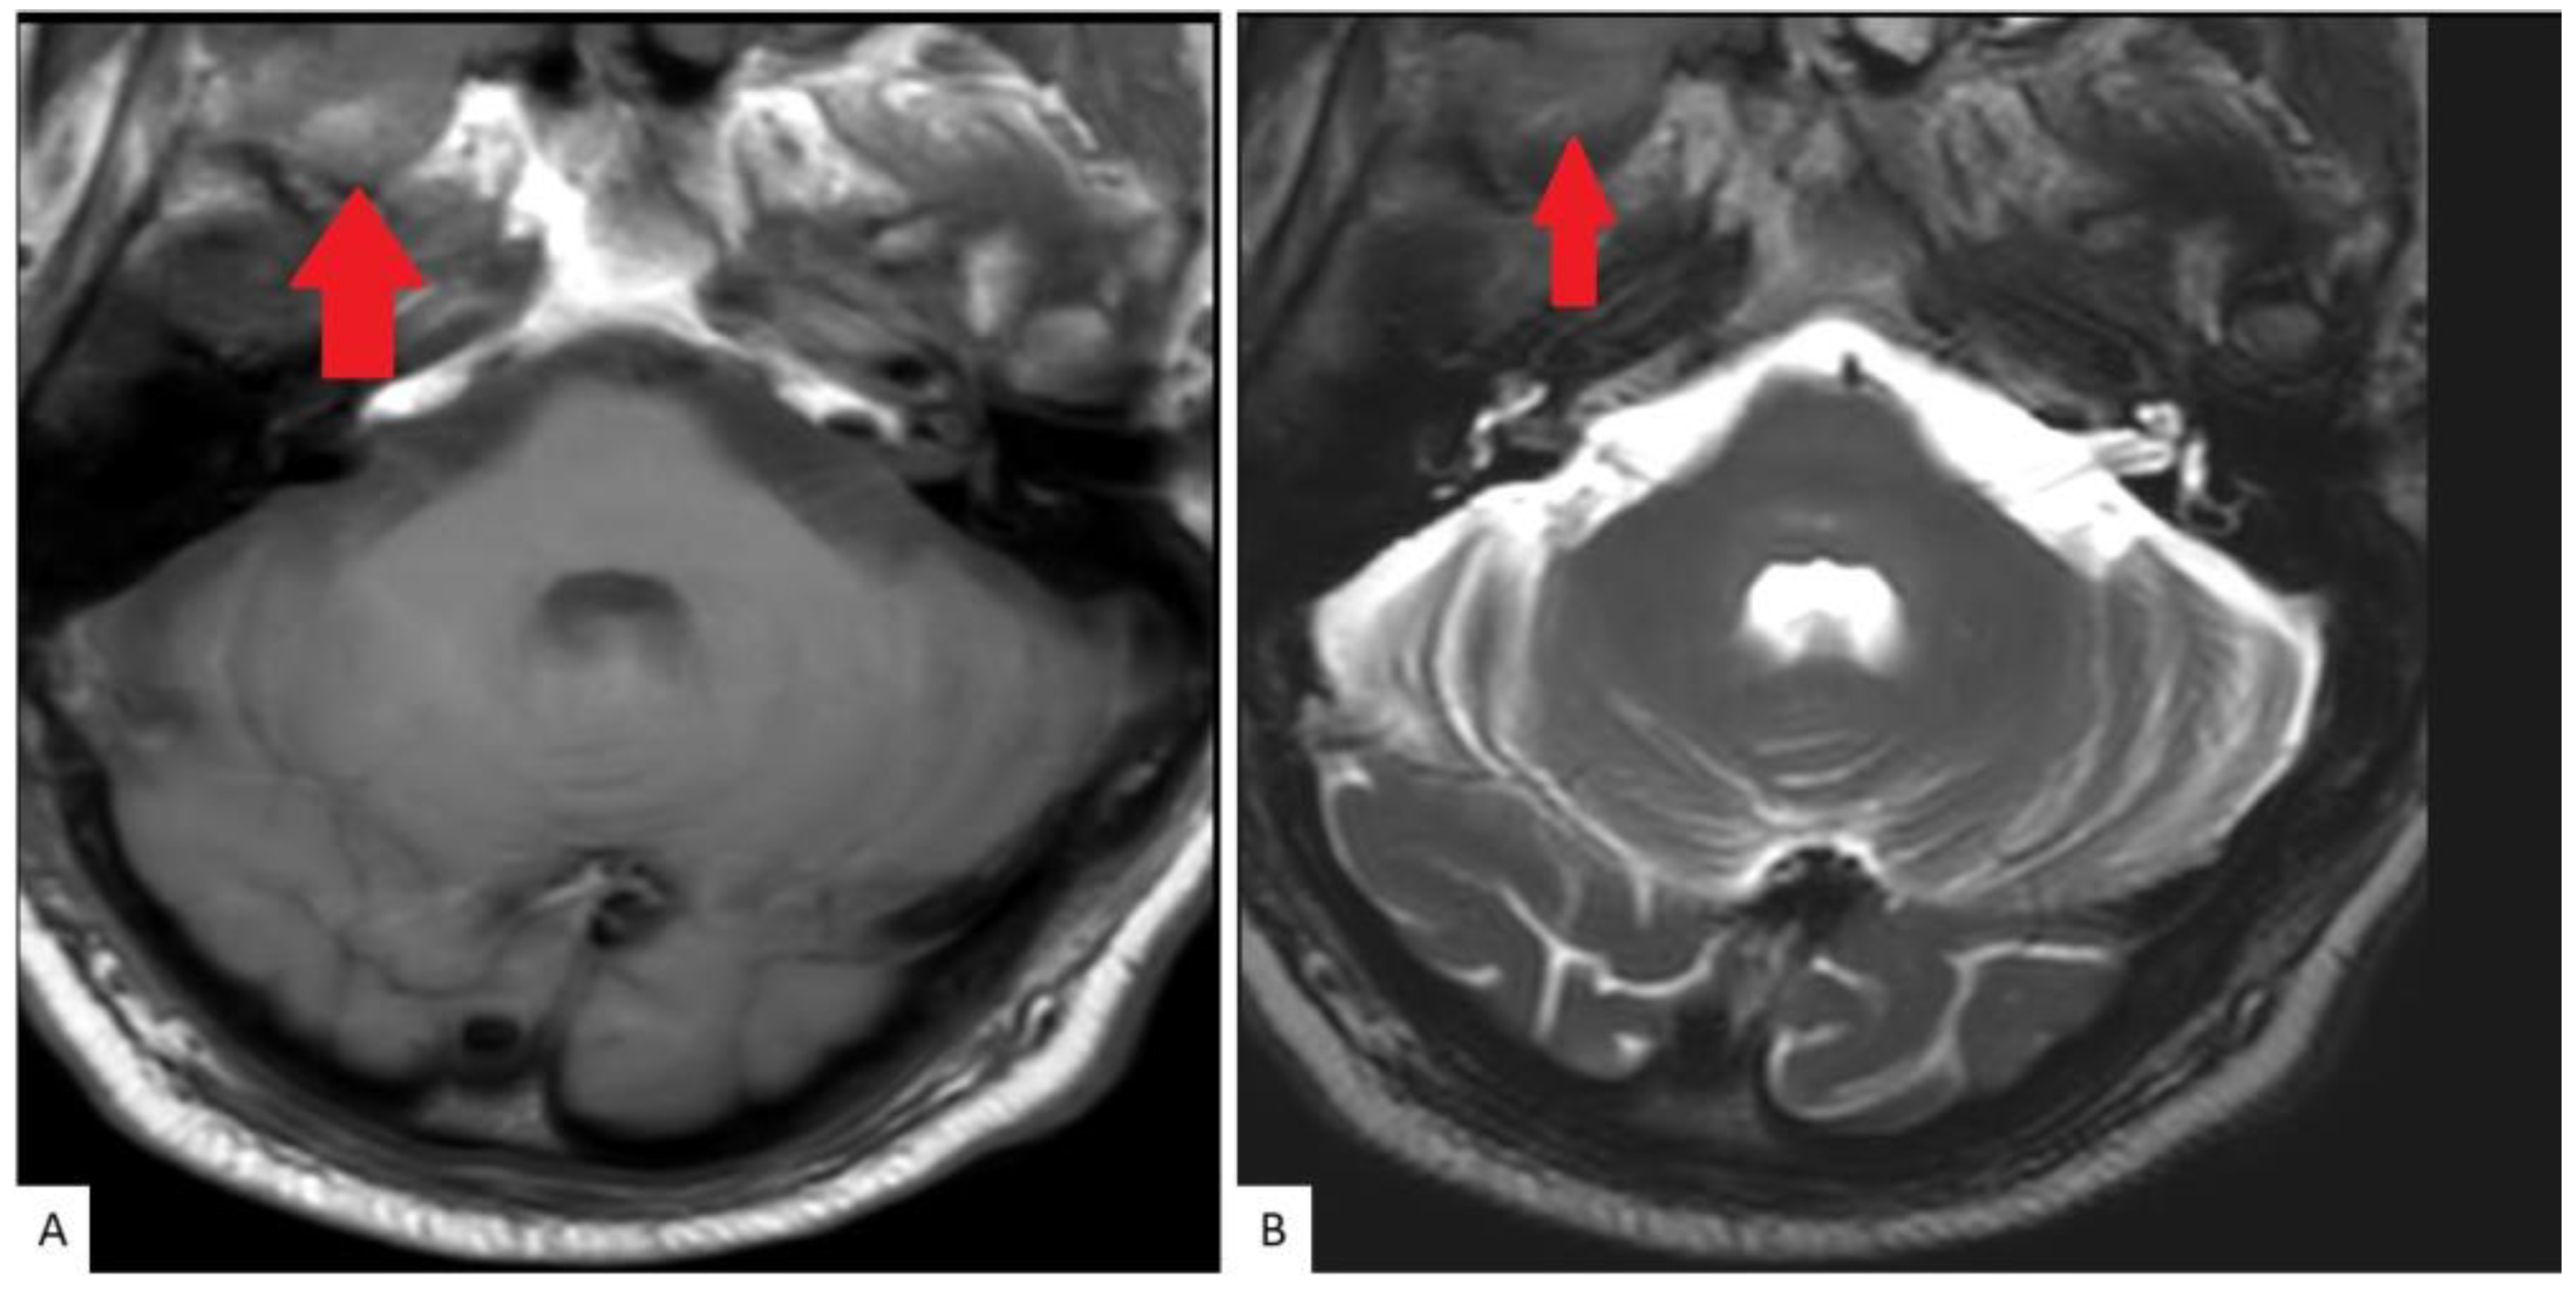

A bone scan showed a right maxillary sinus mass extending into the orbital floor, as well as increased activity from the proximal right femur to the mid shaft, and the left sacrum. A cardiac MRI revealed an irregularly shaped mass invading the superior vena cava and up to the atrial free wall (Figure 1). The X-ray of the right femur showed a large lytic lesion and multiple small lesions in the proximal right and left femur (Figure 2). Magnetic resonance imaging (MRI) of the brain and cervical spine further confirmed the right maxillary sinus mass extending through the orbital floor and into the pterygopalatine fossa and inferior orbital fissure (Figure 3).

Figure 3.

MRI Cervical spine: Axial T1 (A) and T2 (B) weighted images as part of a cervical spine MRI demonstrate a soft tissue lesion centered in the right maxillary sinus involving the masticator space (red solid arrow).